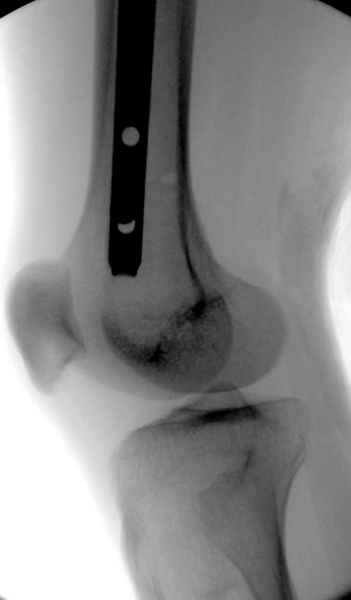

Как раз недавно у меня был примерный случай: больному 36 лет, поступил ночью, травма в результате мотоциклетной аварии, кроме чрезвертельного и спирального перелома левого бедра имеется переломы костей предплечья с этой же стороны. Скелетное вытяжение, а на следующий день больной про оперирован на ортопедическом столе с дистракцией. Чтобы не расколоть чрезвертельный перелом провели временную спицу ближе к переднему кортексу, из малого разреза костодержатель для репозиции, а фиксацию провели антиградным штифтом. Этапы операции на снимках.

DK> фиксацию провели антеградным штифтом.

Да, сейчас это и у нас самый напрашивающийся выбор. Сделали гвоздем ChM, картинки в приложении.

Больной долго оставался нестабильным, только на 14 день удалось заменить на антеградный интромедуллярный штифт TFN (trochanteric femoral nail) SmithNephew. После неудачной попытки закрытой репозиции, несмотря на использование "joystick", проксимальный стержень от

наружного фиксатора, (перелом начал срастаться) репозицию провели из малого доступа, затем остальные этапы операции.

Случай был представлен из-за того, что больного оперировали после наружной фиксации и был риск инфекцирования через места проведения стержней (на снимках), прошло больше 3 месяцев, выписан из амбулаторной службы из-за отсутсвия надобности дальнейшего наблюдения.